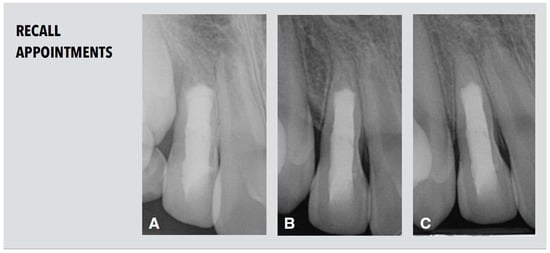

The patient attended the first recall appointment nine months after root canal filling. The tooth remained asymptomatic. Healing of the apical lesion and a considerable increase in both root length and thickness in the apical part below the MTA level was visible in the periapical radiograph (Figure 5A). Further root maturation was detected two years after treatment (Figure 5B).

Figure 5.

Radiological follow-up. (A) Periapical radiograph after nine months demonstrating increase in both root length and thickness in the apical part below the MTA level. (B,C) Periapical radiographs after two years (B) and after three years and nine month (C) demonstrating further root maturation.